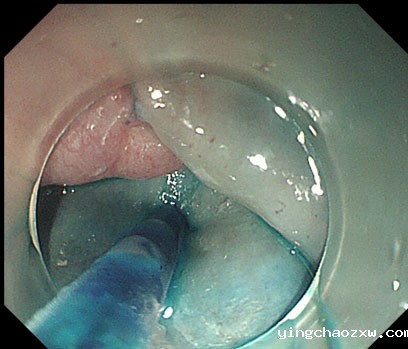

内镜下曲张静脉硬化剂注射